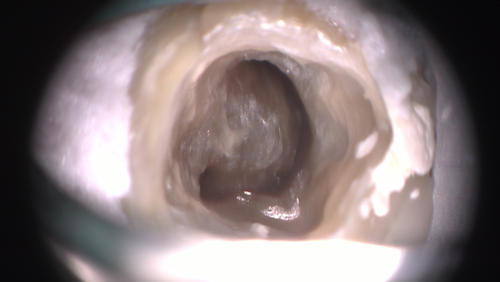

下の写真が樋状根ですが、「根管」よばれるような管ではないことが解ると思います。

管ならこんなドリルで拡大形成することはある程度は可能ですが、このような溝のようなところにドリルを入れても無駄です。空振りするだけですね。